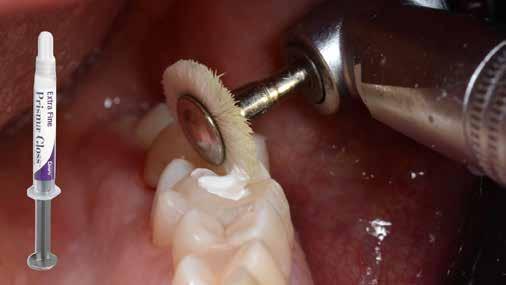

A Palodent V3 matricarendszer felhelyezését követően a zománc 10 másodperces szelektív savazása, majd lemosása és leszárítása után történt a kavítás bondozása Prime & Bond Universallal.

A restauráció megfelelő polimerizációja után célszerű a kofferdám nyújtotta retrakciót kihasználni, és a restauráció széli záródásában levő esetleges kompozitfölösleg elfinírozását jobb rálátás mellett elvégezni (9. ábra). Ebben nagy segítségünkre lehet az Enhance rendszer, mely a kompozitot nagyon szépen elsimítja, de a természetes fogszövetet nem bántja.

A matricázott terület széli záródásának a kidolgozásában az EVA polírozó (10. ábra) lehet a segítségünkre, amellyel a gingiva sérülése megelőzhető, és a kialakított feszes kontaktpont sem kerül redukcióra (11-12. ábra)

A kofferdam eltávolítását követően kerülhetett sor az occlusio beállítására csücsöklejtők domborúságának a redukciója révén (13. ábra). A harapás gyémántfúrókkal történő beállítása után a polírozás Enhance rendszerrel történt, melynek végső lépéseként a PrismaGloss használatával (14. ábra) nyerhette el a restauráció a végső fényességét (15. ábra)